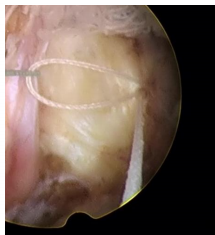

脊柱修復(fù)與重建技術(shù)之纖維環(huán)縫合術(shù)是在各種針對椎間盤突出癥的手術(shù)術(shù)式輔助下,閉合纖維環(huán)上殘留的破口,技術(shù)特點(diǎn)如下:

1、纖維環(huán)縫合手術(shù)是對椎間盤形態(tài)進(jìn)行的修復(fù),促進(jìn)了纖維環(huán)破口的愈合,是對以纖維環(huán)破裂所造成的椎間盤突出癥直接和有效的治療手段。

2、即刻閉合纖維環(huán)的破口,顯著降低椎間盤內(nèi)殘留髓核受力后從纖維環(huán)破口處再突出的復(fù)發(fā)幾率。

適用于椎間孔鏡、椎間盤鏡、雙通道脊柱微創(chuàng)手術(shù)技術(shù)(UBE),顯微鏡、通道管等微創(chuàng)手術(shù)髓核摘除后纖維環(huán)的修復(fù),降低術(shù)后復(fù)發(fā)率